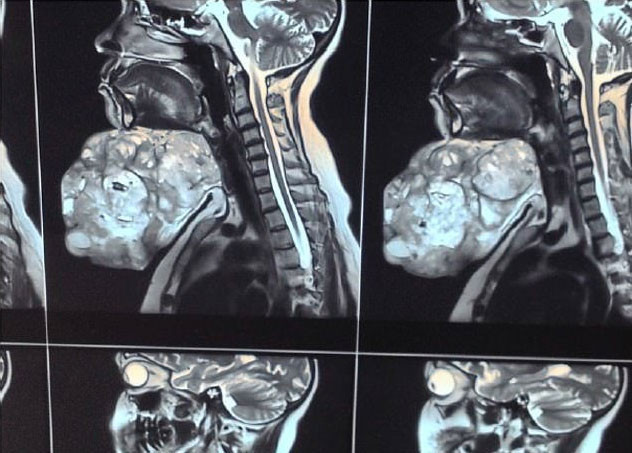

HİNDİSTAN'da tıp tarihine geçen ve literatüre girecek bir ameliyat gerçekleşti. 47 yaşındaki kadının çenesinin altından 4.5 kilo ağılığında 30 santim uzunluğundaki tümör alındı...

TIP dünyası Hindistan'da gerçekleştirilen bir tümör ameliyatını konuşuyor. 47 yaşındaki kadın hastanın çenesinde çıkan ve neredeyse 20 yılda devasa boyutlara ulaşan tümör başarılı bir operasyonla alındı. Ameliyattan önce boynunu hareket ettiremeyen kadındaki ameliyat öncesi ve sonrasındaki hali inanılmazdı. İşte İngiltere’nin saygın tıp yayınlarından British Medical Journal (BMJ), Hindistan’ın Uttar Pradeş eyaletinde yaşayan 47 yaşındaki bir hastayla ilgili haberi...

Adı açıklanmayan hastanın çenesinde 18 yıl önce bir tümör oluştu. Doktor kontrolünde takibi yapılan tümör, giderek büyümeye başlayınca hastaya operasyon yapılması gerektiği söylendi.

Ameliyat olmaktan korkan ve operasyona yaklaşmayan hasta, aradan geçen yıllarda bu kararından pişman oldu. Zira tümör 4.5 kilo ağırlığa, 30 cm uzunluğa ulaşmış, kadın kafasını hareket ettirmekte bile zorlanmaya başlamıştı.

Korkusunu yenen ve doktora başvuran kadın saatler süren başarılı operasyonun ardından tümörden kurtuldu. Çenesine yapılan estetik müdahaleyle tümörün bütün izlerinden kurtulan kadın sağlığına kavuştu.